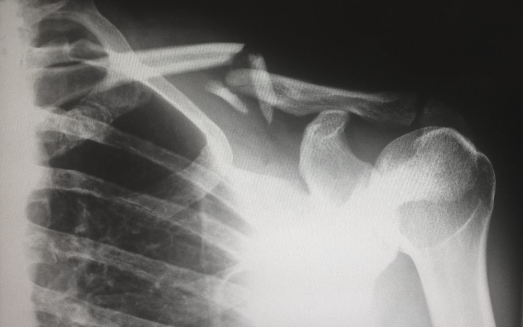

But now, doctors are scared. They want to try anything but opioids. I asked her about surgery, and she said her doctor recommended against it. He said the odds are roughly 50-50 that it would do more harm than good. She got an electrical stimulator implant, like a pacemaker, surgically inserted below her waist, with electric leads running on either side of the spine.